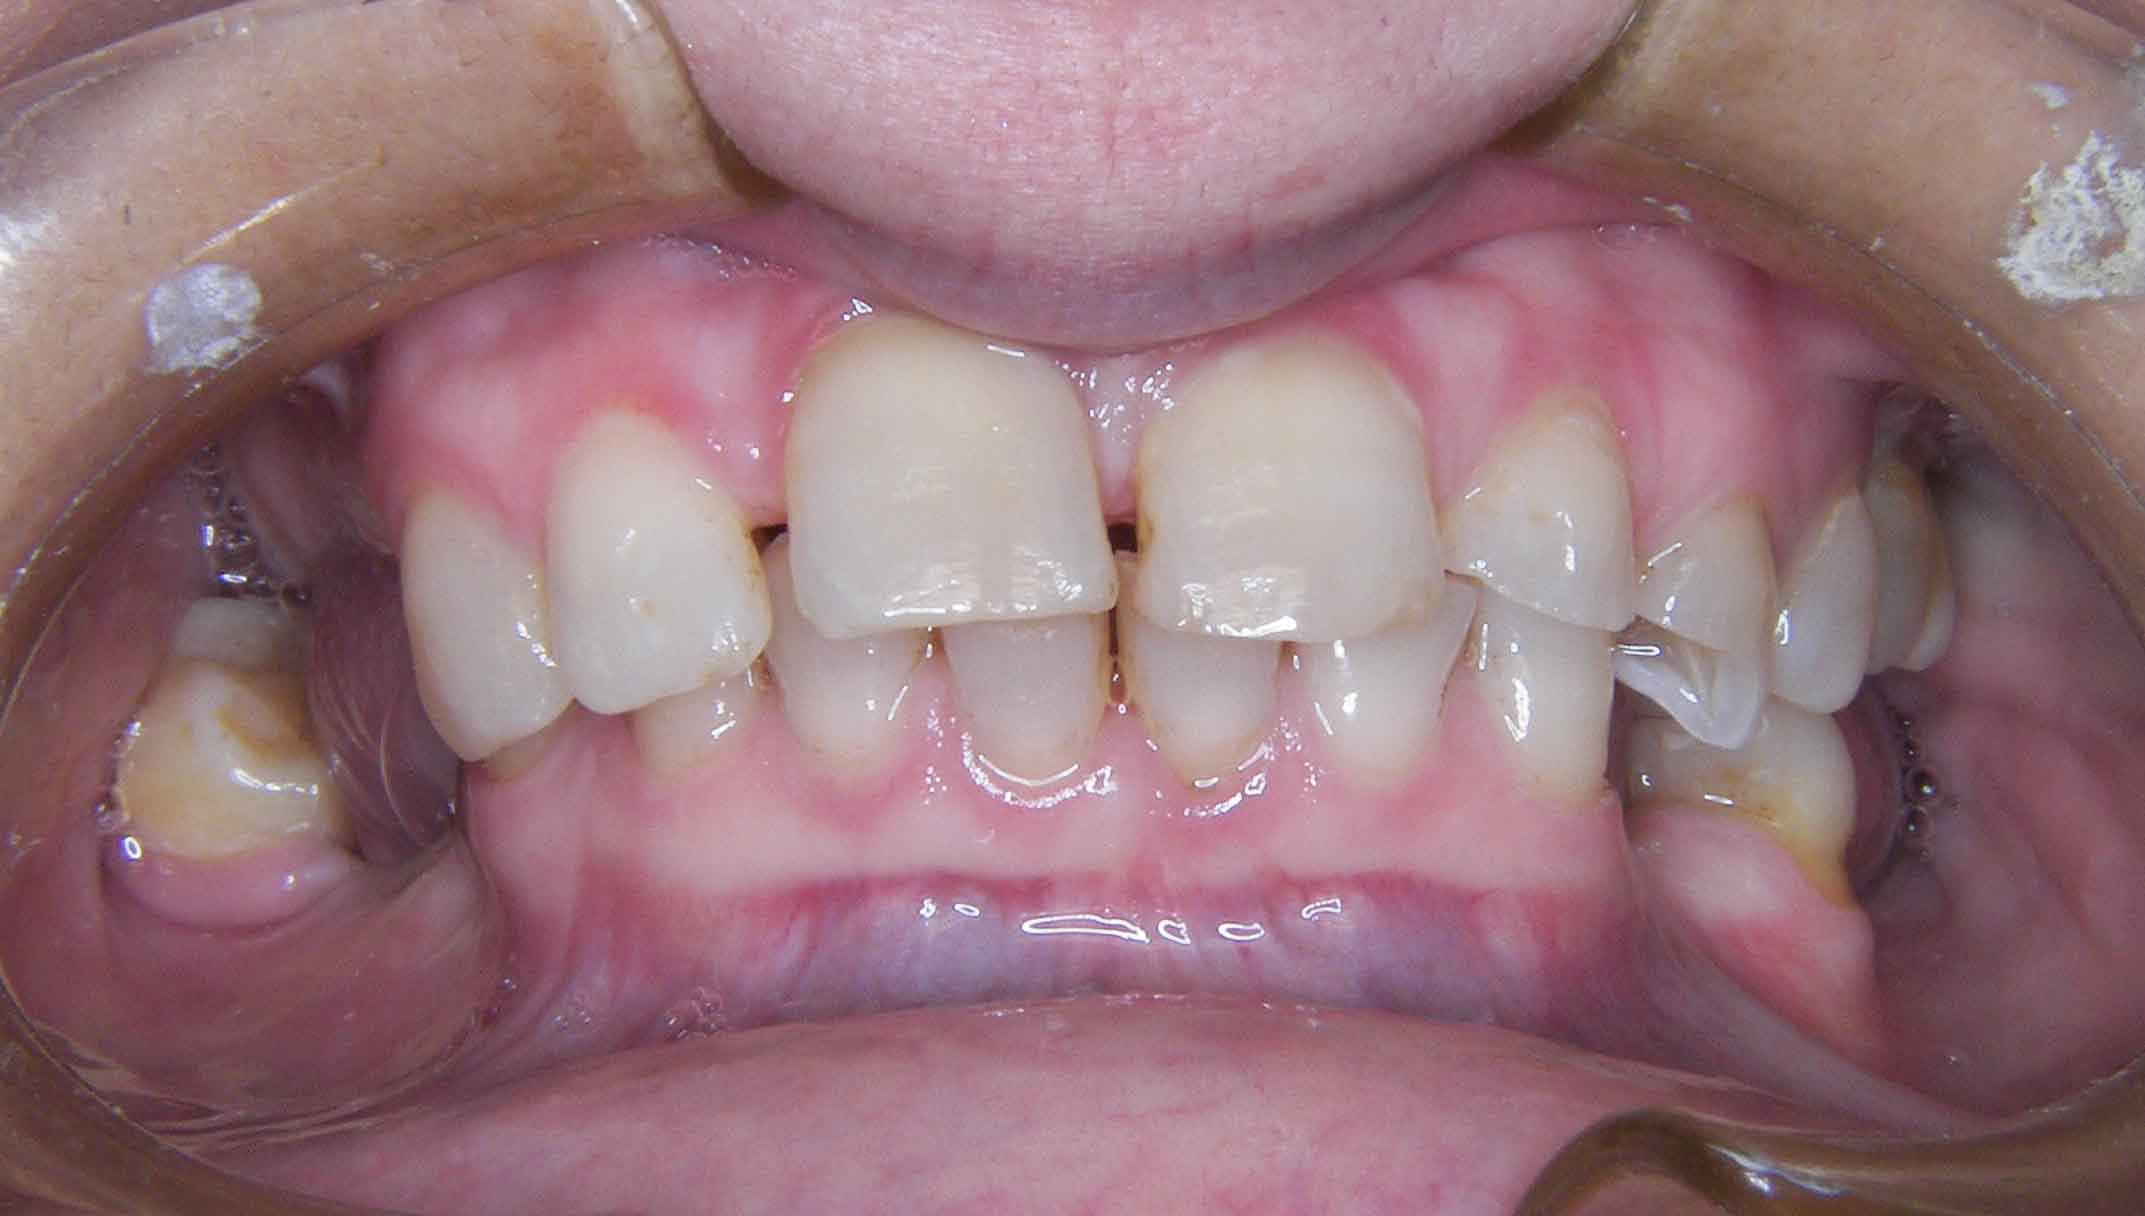

Paciente com limitações funcionais e estéticas graves

Alterações de Cor por Tetraciclinas

Problema Principal

Alterações de cor devido a utilização de Tetraciclinas em criança. Vários tratamentos feitos ao longa da vida para disfarçar o problema sem resultados satisfatórios.